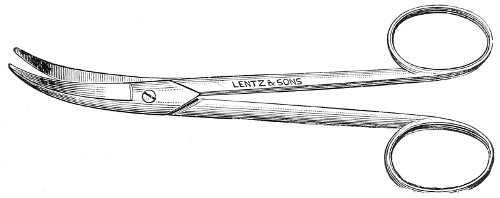

Fig. 24.—Emmet’s perineal scissors.

Fig. 25.—Curved scissors for denuding.

The secondary operation is performed at any time after cicatrization has occurred—often many years after the receipt of the injury. This operation is at present one of the commonest in gynecology, because the injury is not detected, is neglected, or is improperly repaired after labor. In the secondary operation an anesthetic is necessary. The mucous membrane must be removed or denuded on the posterior wall and about the mouth of the vagina, in order that the lacerated structures may be brought again in apposition. The denudation is best made by means of scissors curved on the flat (Figs. 24 and 25).